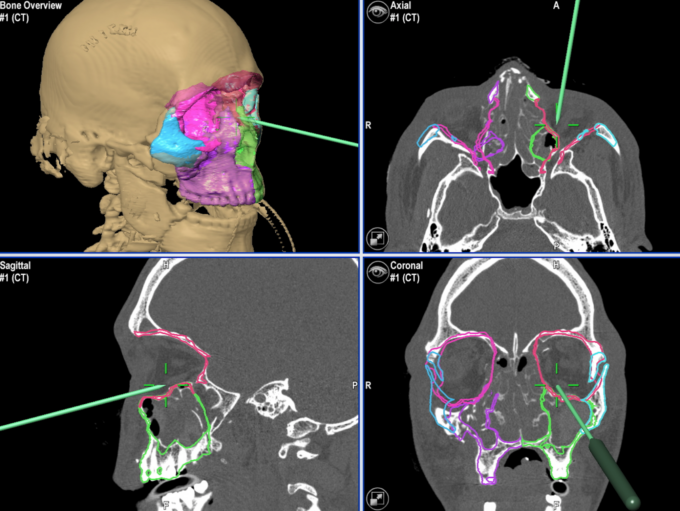

Ieri, mercoledì 2 marzo 2022, al Cto di Torino è stato eseguito un intervento all’avanguardia di circa 6 ore per ricostruzione del volto con navigatore intraoperatorio dei chirurghi maxillo facciali delle Molinette.